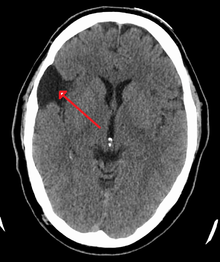

Arachnoid cyst